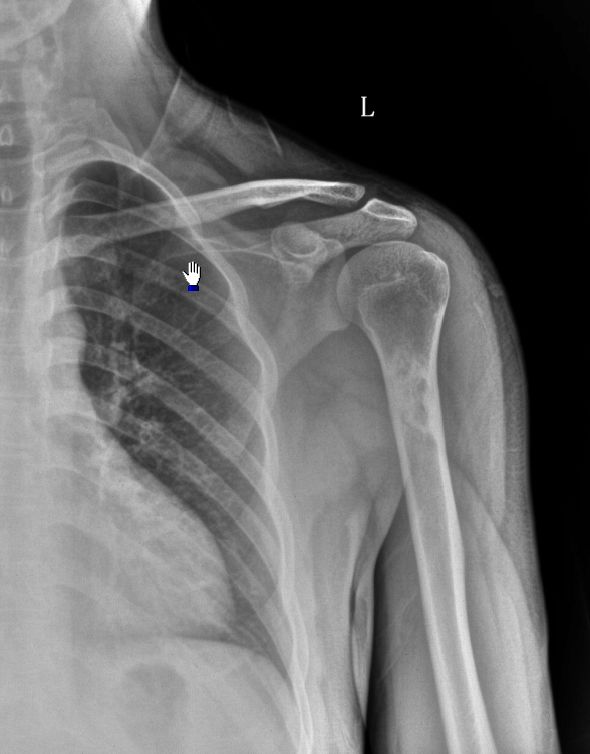

男,25岁,左肱骨上段病变,外伤发现,病人无任何症状。

内生软骨瘤。

内生软骨瘤。建议mri检查。

内生软骨瘤可能,骨梗死待排。

考虑brodie氏骨脓肿。(低毒性骨感染)。

无任何症状,年龄25岁外伤发现,考虑骨纤。

鉴别:brodie氏骨脓肿(低密度囊状影,边界清),内生软骨瘤(环状半环状钙化)。

平片确定的是:良性骨肿瘤或肿瘤样病变。骨纤、内生软骨瘤、非骨化性纤维瘤、brodie氏骨脓肿都有可能!交给ct鉴别!

应做ct,病变如位于骨皮质内考虑骨纤;如病变位于髓腔内考虑内生软骨瘤。

考虑左肱骨上段骨纤维异常增殖症,骨梗死待排。